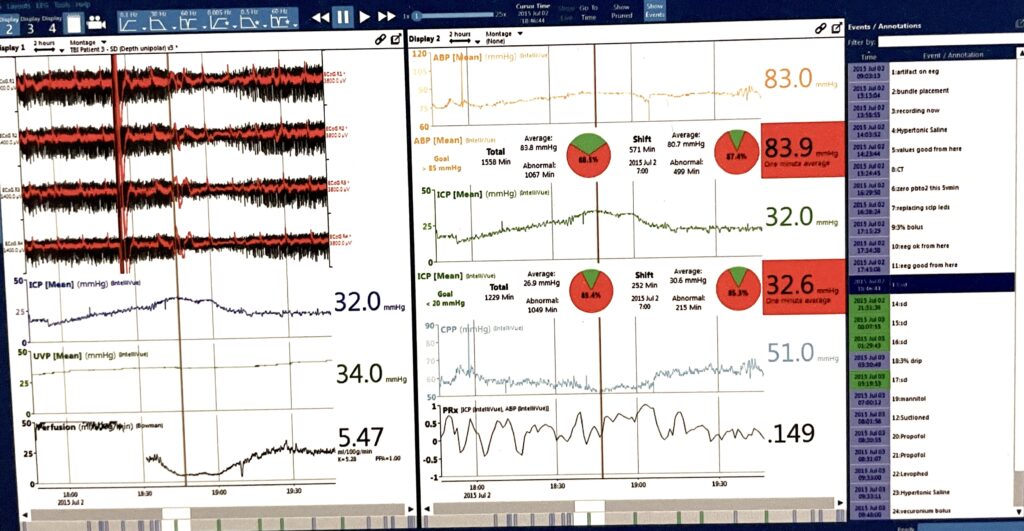

Gary Trapuzzano, VP of R&D, worked with Dr. Jed Hartings for over a year to implement features to record and visualize slow potentials on the CNS Monitor. As a result, it is the preferred system for monitoring spreading depolarizations, an exciting new frontier in brain injury research.

CNS Envision showing spreading depolarizations